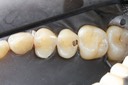

Kyle Chock #14 caries removal